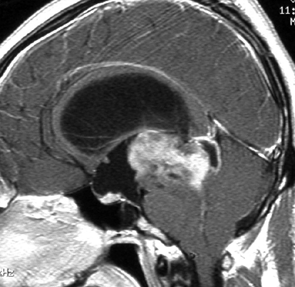

14歳の男の子です。このMRI画像はどう見ても松果体奇形腫 mature or immature teratoma 以外には考えられません。左の写真で脂肪腫が混じっていることが解ります。AFP 130 ng/ml, HCG-beta 30 mIUでしたから,ICE化学療法と放射線治療 (全脳室 25.2グレイ/15分割と局所28.8グレイ,1回線量1.8グレイ)をして少し小さくして(右の写真)から開頭手術しました。全摘出して病理診断は成熟奇形腫でしたが,治療前にはおそらくもっと未熟な部分が混じっていたと考えられます。